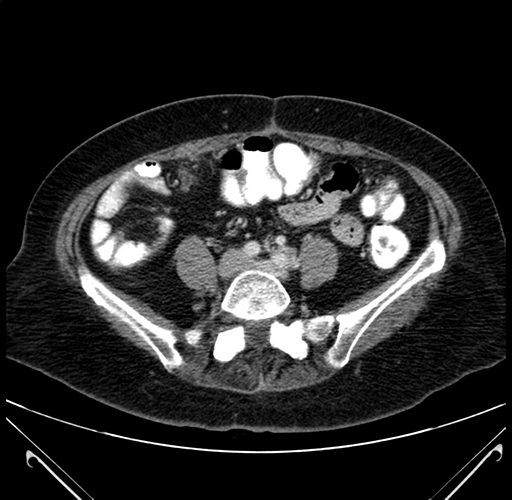

Axial Venous

Imaging analysis

Based on your CT findings, which issue(s) would give reason for "planned slowing down moment(s)" in this case?

Considering a standard right hepatectomy procedure, what step(s) of the operation would you do differently in this case?